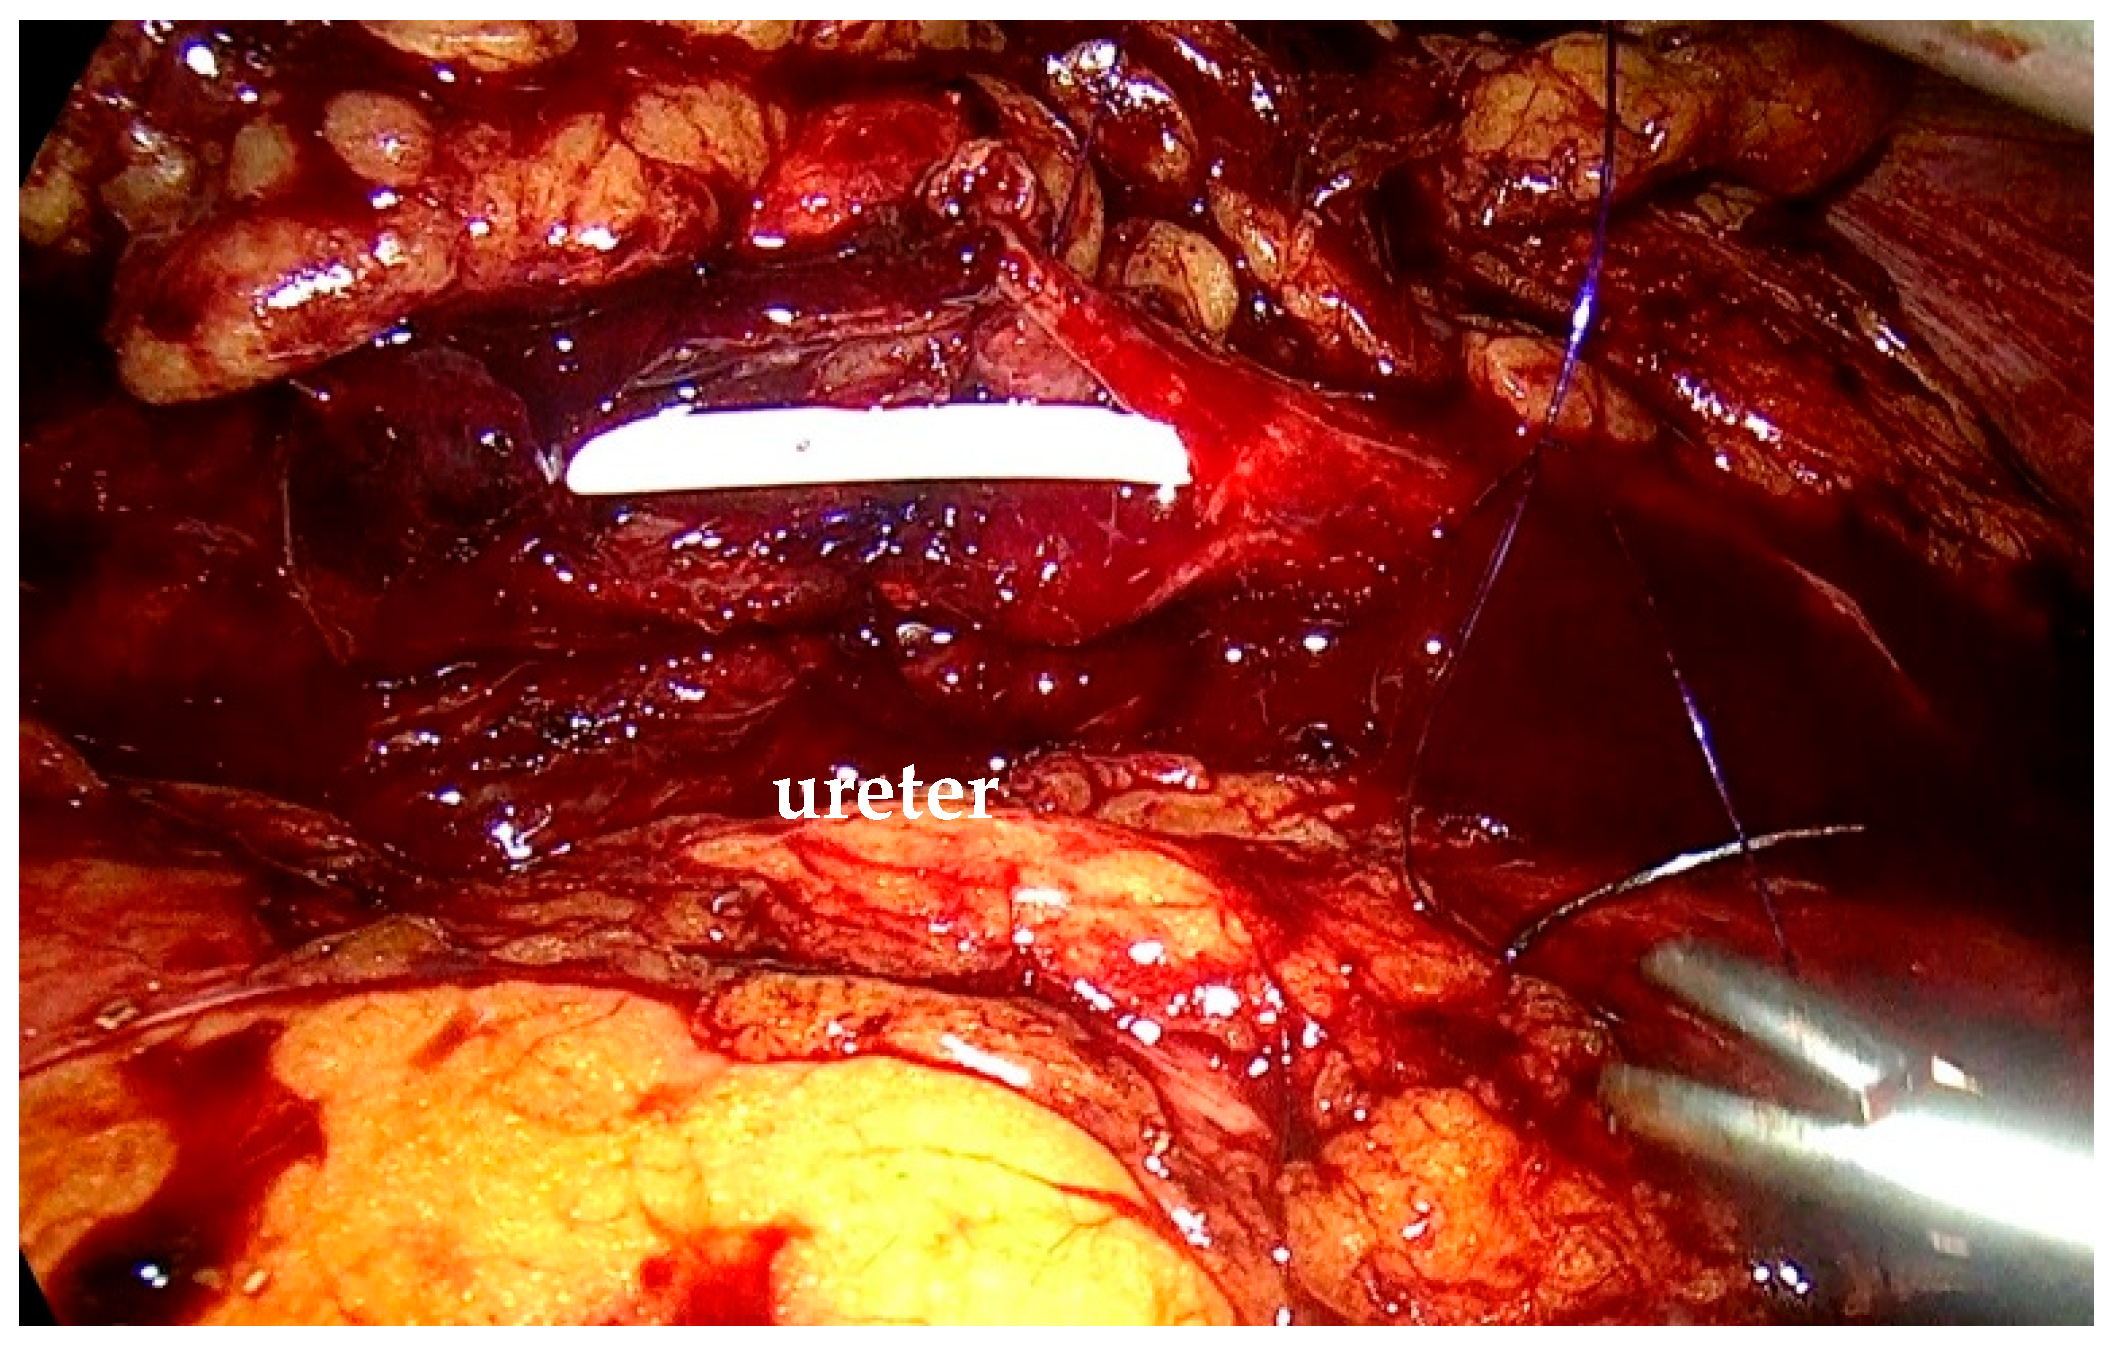

To mobilize the colon, we incised the white line of Toldt, exposed Gerota’s fascia, and identified the ureter (Figure 2).

Figure 2. Isolation of the ureter with the stenotic segment and the dilatated upper ureter.